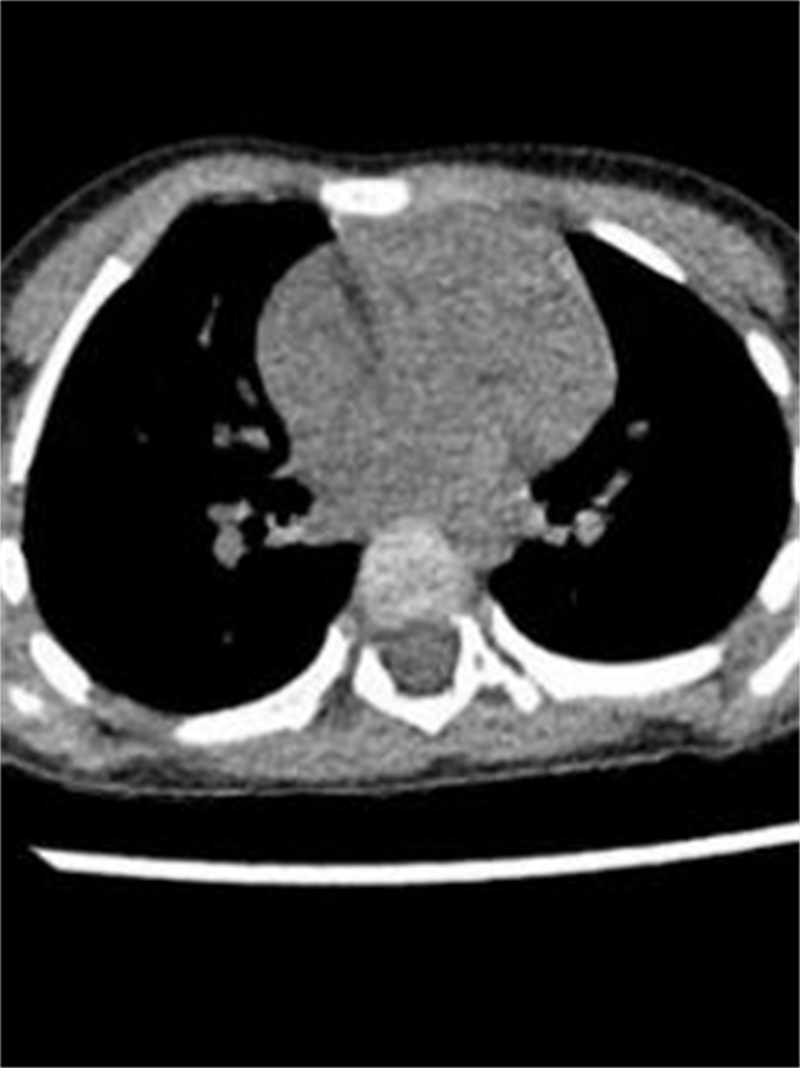

由于肋软骨在X线胸片上不显影,对于肋骨畸形的评价与确诊有局限性,目前多采用胸部 CT加肋骨重建检查。

可以,目前采用悬吊腔镜叉状肋切除术。叉状肋大部分分叉的上部肋软骨发育较细,且生长方向与其他正常肋骨走行角度不一致,这是导致胸壁凸起的原因之一。手术时,通常需切除分叉的上部软骨及分叉的部分硬骨。